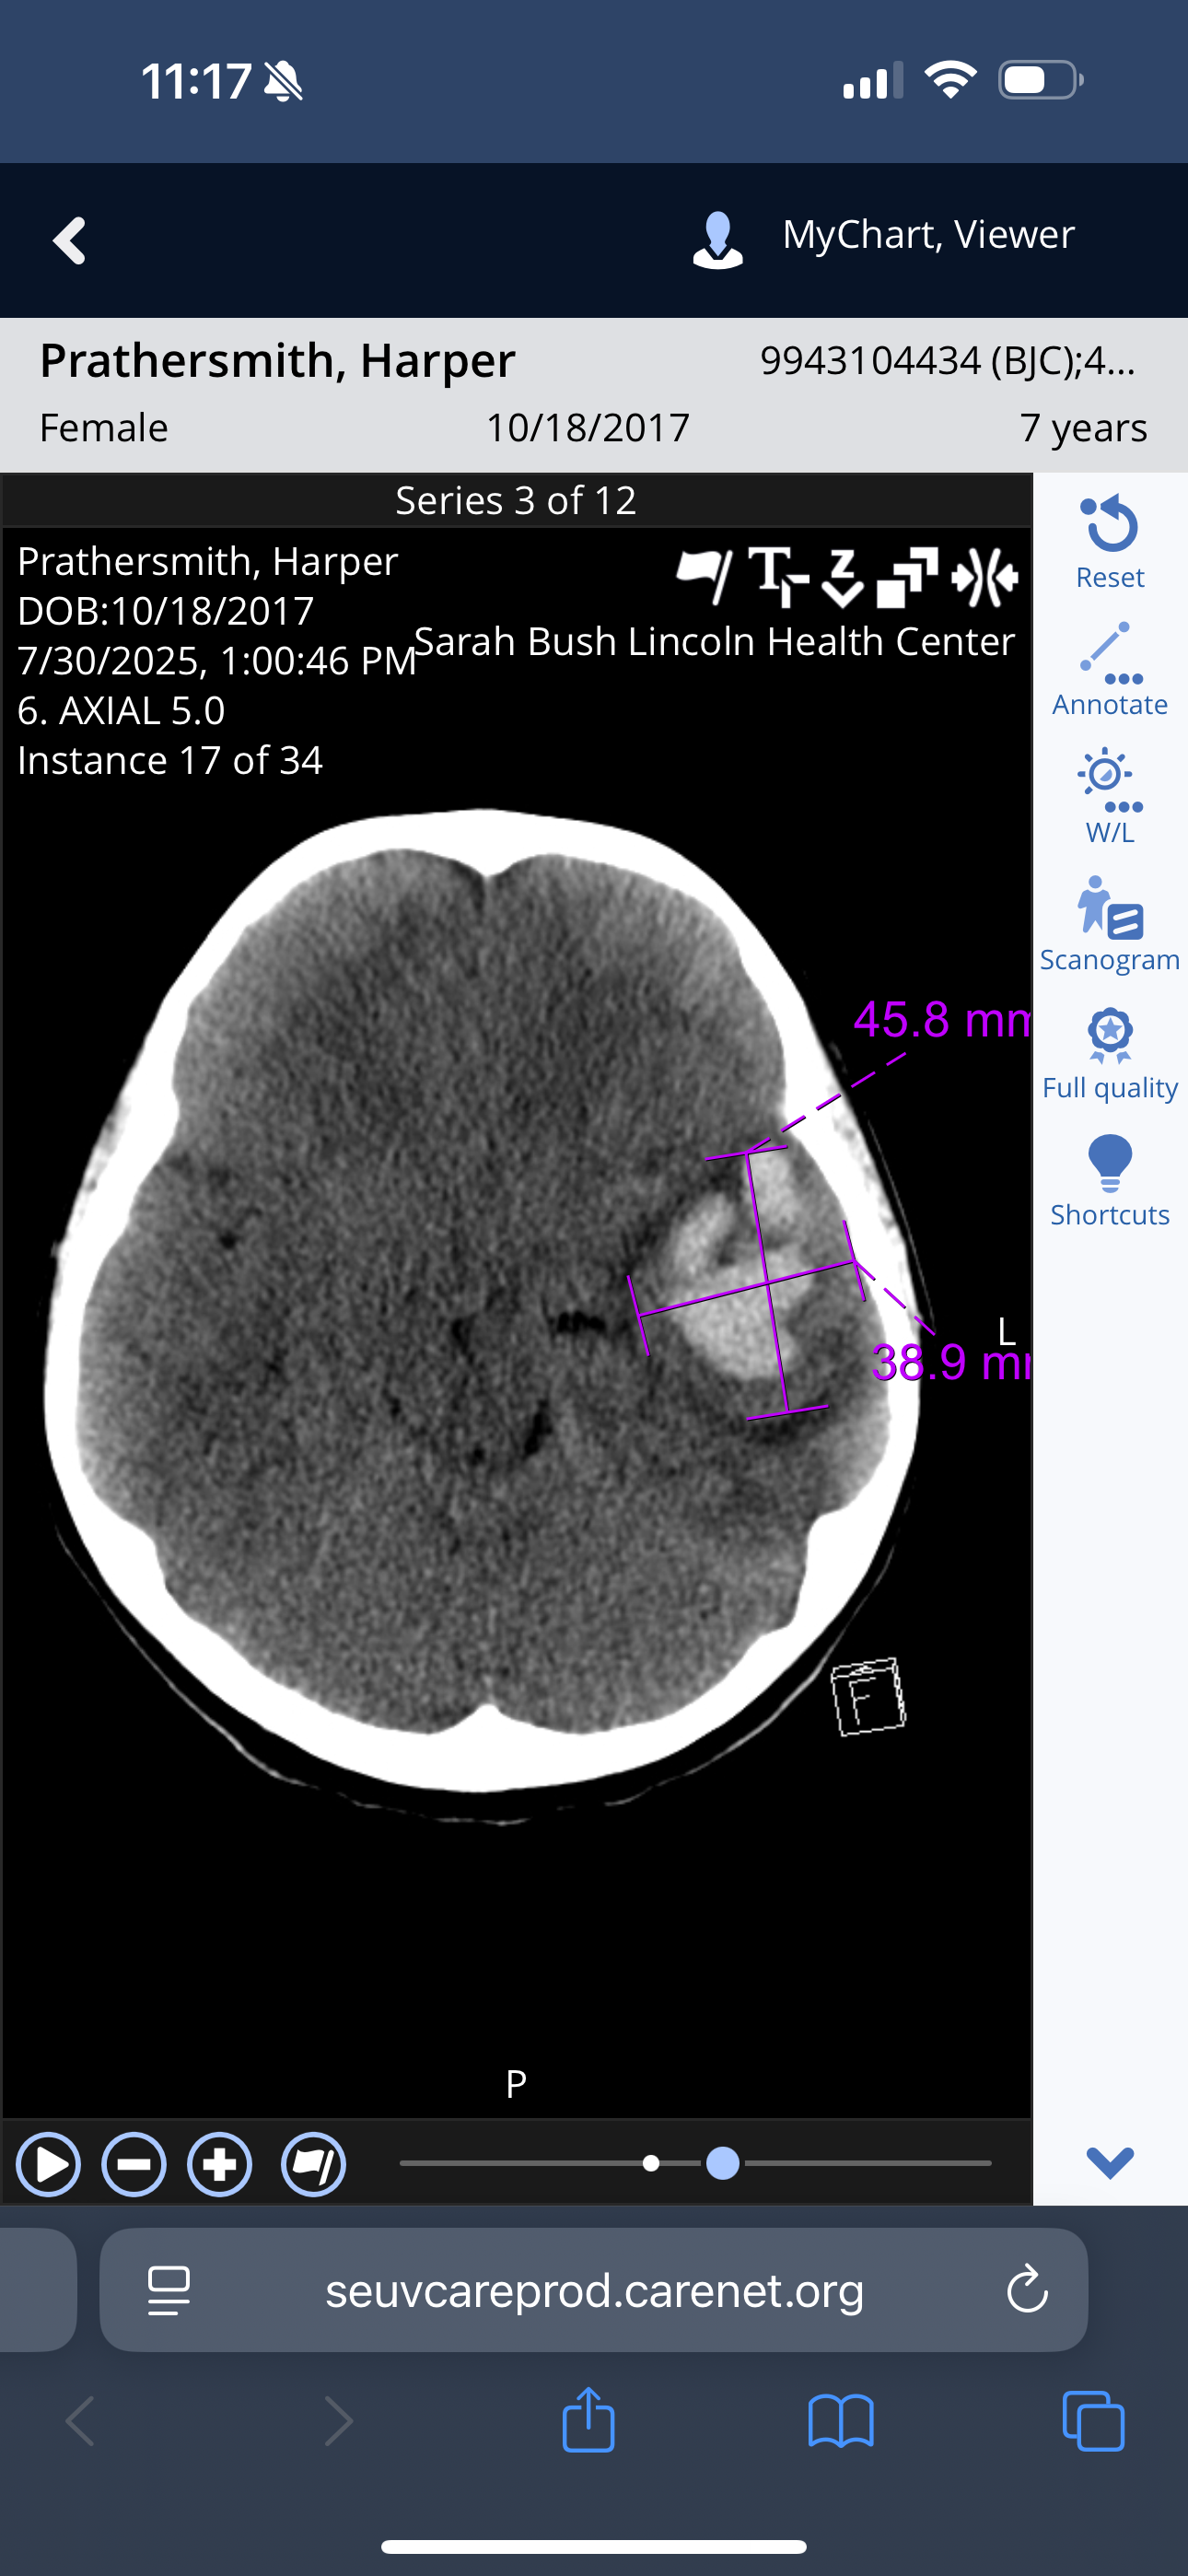

After being admitted around 1am and getting some rest, the hospitalist came to see us around noon and asked us questions, including Harper. She told me that she would like to do a CT scan, and I told her we weren't going home without one. I'm so thankful that we did that scan. Within 6 minutes of being back in the room, she came running in and said she had a 3x3 brain bleed and would be sent via helicopter to St. Louis Children’s for emergency brain surgery. She told me she would return after the phone calls to talk more.

After that CT scan, we were told that she more than likely had an AVM rupture. This is very rare for children to have happened. Around 4pm on July 30th, Nick and the three amazing men took off to take her to St. Louis to save her life.